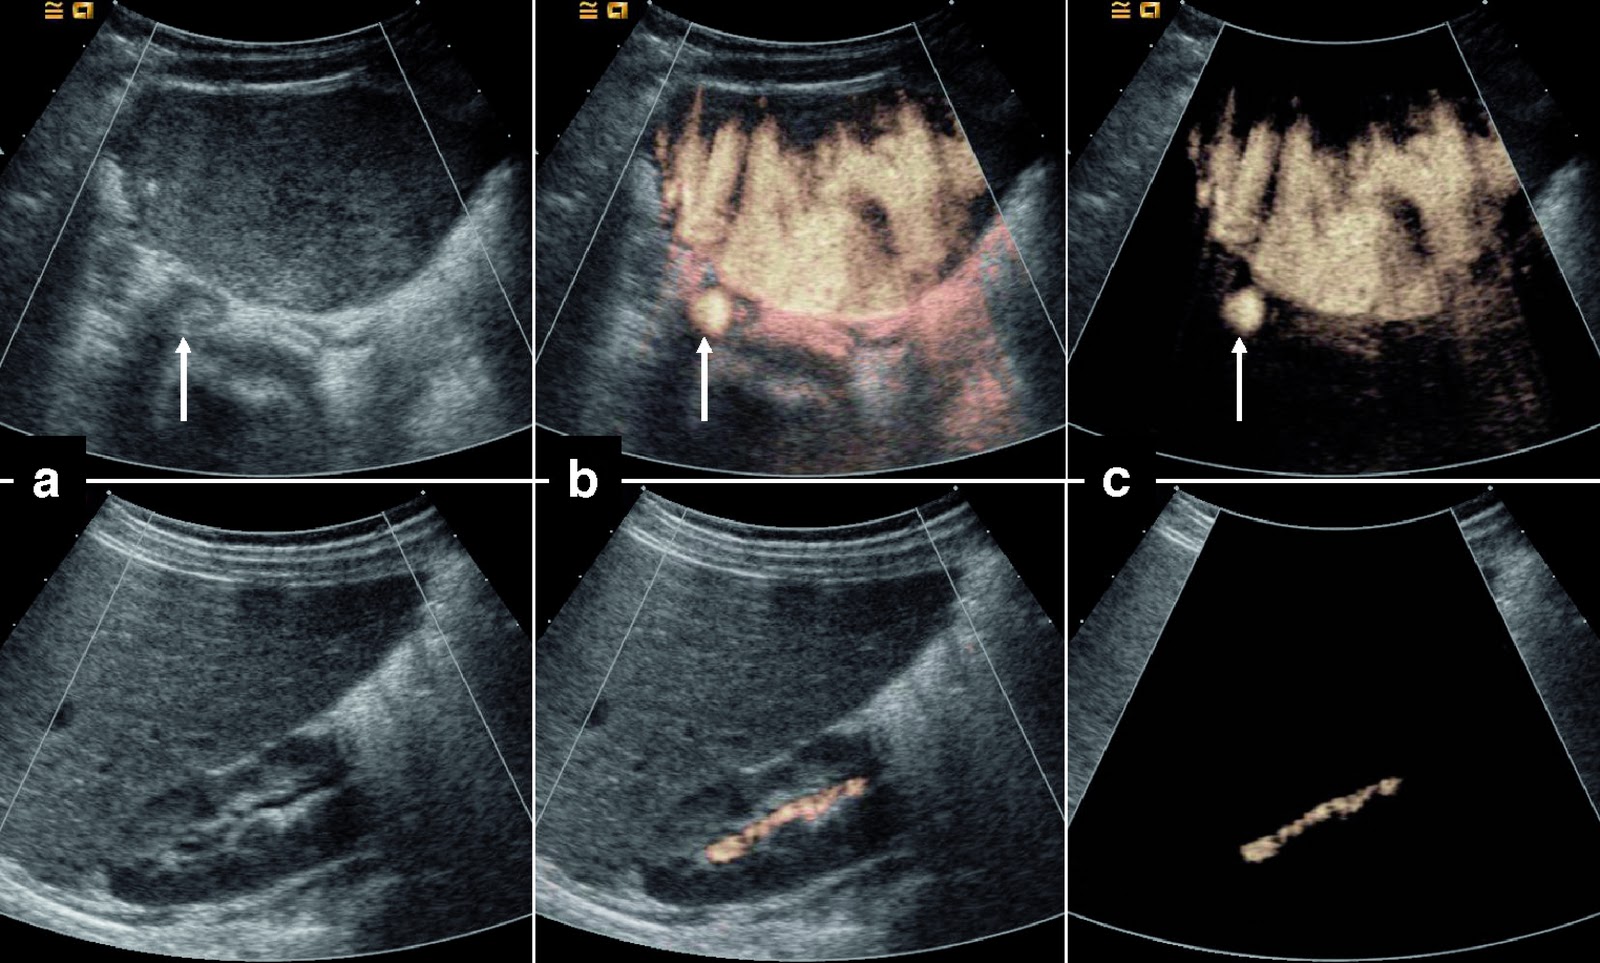

From www.jvascsurg.org

Intraoperative contrastenhanced ultrasound for early diagnosis of Ultrasound Contrast Contraindications Contrast agent administration should be done with either. At present, the only remaining contraindications to ultrasound contrast agent administration are 1) previous hypersensitivity. Contrast echocardiography has evolved into a. Despite significant advances in ultrasound transducer design and signal processing technology, echocardiographic. This has been accompanied by the removal and/or reductions of prior contraindications to use and the provision of new. Ultrasound Contrast Contraindications.